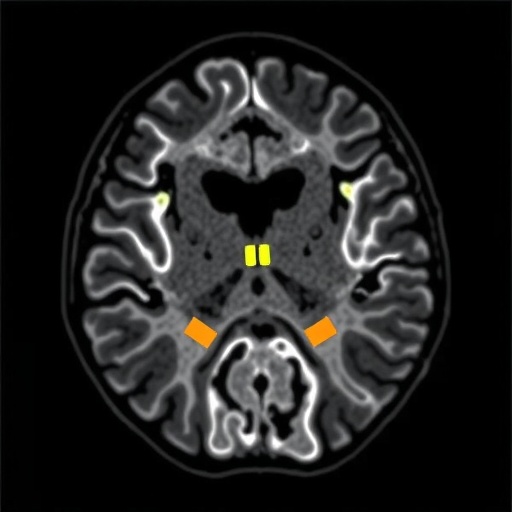

In the pursuit of understanding SWS, researchers have put significant effort into elucidating the magnetic resonance imaging (MRI) features associated with the syndrome. MRI serves as an invaluable tool in identifying both the structural and functional anomalies present in affected individuals. Recent studies, particularly the comprehensive review conducted by Cerron-Vela et al., aim to catalogue these imaging findings, highlighting the evolution of vascular changes from infancy through adulthood, and drawing correlations between imaging findings and clinical outcomes.

On MRI, patients with SWS typically display leptomeningeal angiomas, which are abnormal growths of blood vessels in the protective membranes surrounding the brain. These angiomas can lead to localized ischemia and other complications, significantly impacting the patient’s neurological health. Over time, these vascular changes may progress, culminating in cortical atrophy, white matter changes, and even the development of tissue necrosis, which can further exacerbate clinical symptoms and complicate treatment plans.

One of the most critical aspects of the research is the focus on the timing and nature of vascular responses to the underlying pathology. Early vascular responses may include hyperperfusion, where affected areas of the brain exhibit increased blood flow. This finding can sometimes mask underlying ischemic issues during initial imaging studies. As the condition progresses, however, hypoperfusion tends to dominate, posing challenges for patient management and necessitating careful monitoring of neurological status.